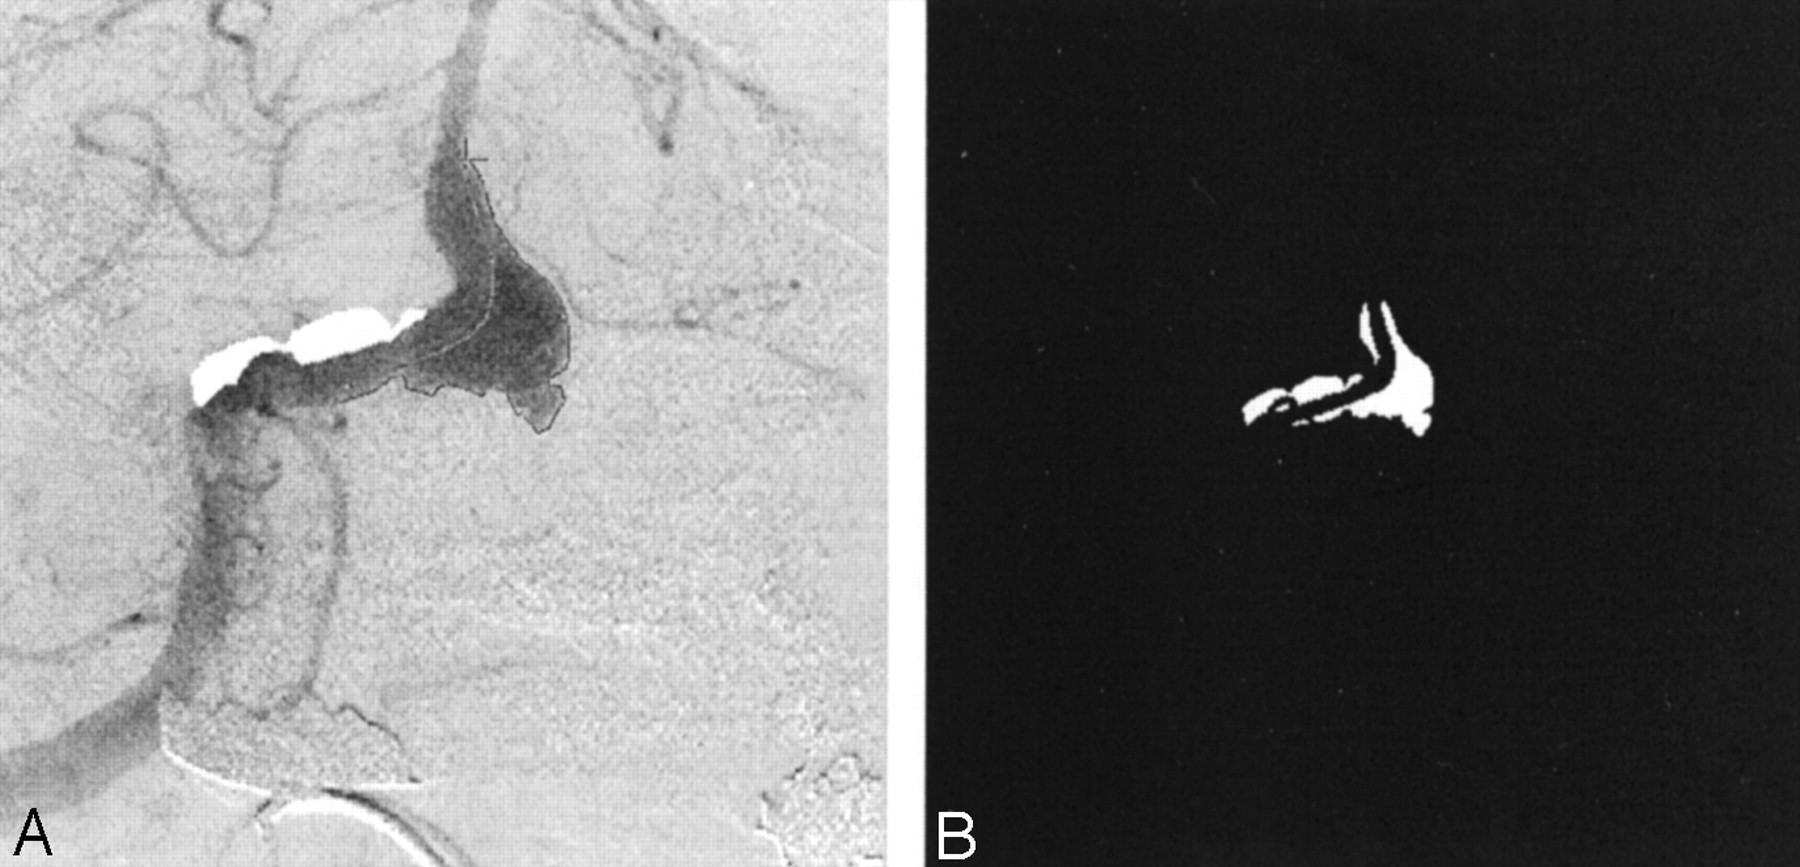

The frame in which the aneurysm was most clearly visualized was chosen in each angiographic run, and a polygonal region of interest (ROI) was manually traced around the aneurysm (Fig 3A). The ROI was traced by starting at the point where the aneurysmal projection in the frame deviated from the course of the normal artery. The tracing continued along the outer edge of the aneurysm and closed along the estimated edge of a normal artery at the aneurysmal neck. When arteries or draining veins are interposed with the aneurysmal mask, they erroneously contribute to the total gray-scale level when contrast material passes through them. In such cases, multiple ROIs that bypassed those arteries or veins were selected to generate the final mask (Fig 3B). That is, if any superimposing vasculature lay in the path of an ROI being traced, that ROI was closed by tracing back along the edge of the superfluous artery or vein. Another ROI was then started at the intersection of the path of the regular ROI trace and the other edge of the imposing vasculature. This mask was multiplied with the entire sequence of frames in a run that delineated the ROI in each frame. The average gray-scale intensity (total gray-scale value of pixels/total number of pixels) within the ROI was then calculated for each frame. Figure 4 shows the variations in average gray-scale intensity with time (raw concentration time curves), before and after stent insertion, from the in vitro experiment and from the anteroposterior (AP) projection data in patient 1.

Images in patient 1.

A, Angiogram illustrates the selection of an ROI.

B, Final mask.